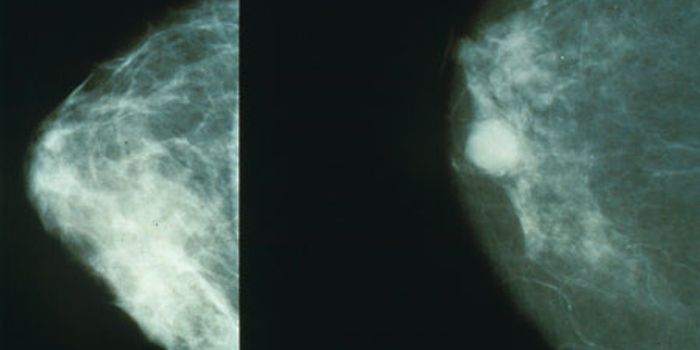

APR 02, 2019CancerThe primary goals of metastatic breast cancer treatment are to ensure that the patient has the longest survival pos ...